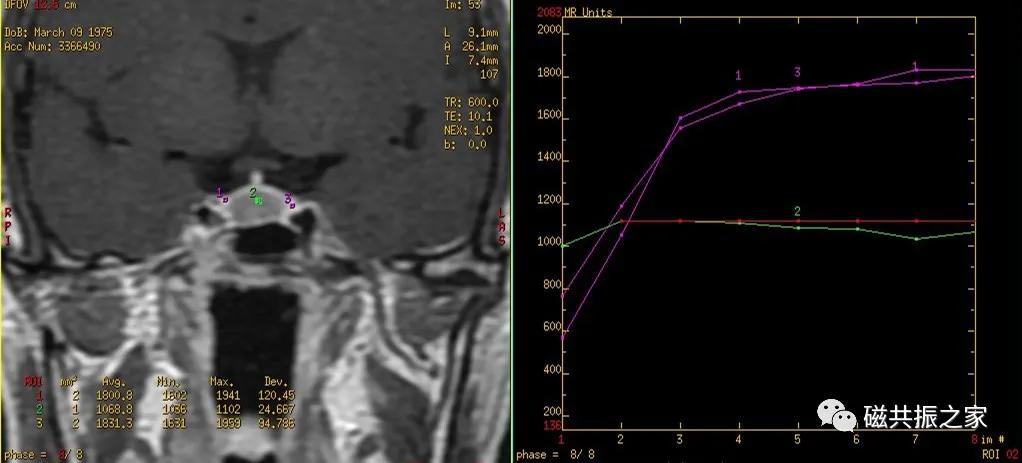

冠状位:COR Dynamic T1 FSE 冠状位T1多期动态增强序列

以矢状位和横断位作为参考定位。定位方法同上面的平扫序列,双侧对称扫描,扫描范围包括整个垂体,为了保证时间分辨率,扫描层数不宜过多,5-7层。注射对比剂前先扫描一期蒙片,暂停,然后注射对比剂的同时开始连续的动态扫描(1.5T:8-10期,每一期20S左右最佳,3.0T:15-20期,每期10S左右最佳),整个动态增强序列扫描3min左右即可。

动态增强通常采用冠状面扫描。注射对比剂前扫描一期蒙片的目的:评估扫描所得的图像质量是否能满足诊断要求,包括范围、信噪比,伪影等。

注射对比剂的同时开始连续的动态增强扫描;也有采用注射对比剂后延迟5s后,再开始扫描的,这两种扫描方式均可。

扫描后的图像做动态增强曲线后处理分析。

根据垂体的血供关系,垂体增强化顺序为垂体漏斗部及后叶、垂体柄、垂体前叶。

垂体无血-脑屏障,在注射造影剂后的早期即可发生强化,而大多数的微腺瘤由垂体的门脉系统供血,其强化比正常垂体慢,在注射造影剂后早期表现为弱强化或不强化,延迟期较正常垂体强化或不强化;但也存在少数的微腺瘤由颈内动脉直接供血,在增强早期也会发生强化。

据部分文献报道在注入对比剂早期即30-90S和1-3min为垂体微腺瘤的最佳对比时间。